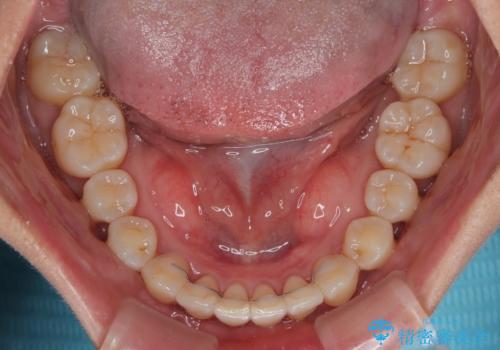

上顎最後臼歯は極端に外側を向いており、下顎骨に対して上顎骨が前方に位置していたため、補助装置により最後臼歯を一気に内側に引き込むとともに、上顎臼歯を後方移動させ、奥歯の咬み合わせが改善した後に、上下インビザラインにより歯列全体を整えていくこととしました。

奥歯の咬み合わせを事前に望ましい位置に改善したことで、インビザライン単独では改善が最も困難な状況を排除することができ、非常に理想的な仕上がりとなりました。